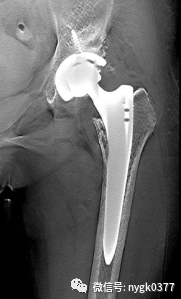

视金识功能去金属伪影功能

基于断层融合图像,智能提取金属假体,把金属假体与骨骼图像有效的区分及组合。使金属假体与骨科图像均可以清晰显示。在视金识图像上即可以清晰的观察金属假体又可以细致的分析假体与骨骼之间的关系。对关节置换术后恢复的观察,翻修术的术前分析起到了有效的影像支持。